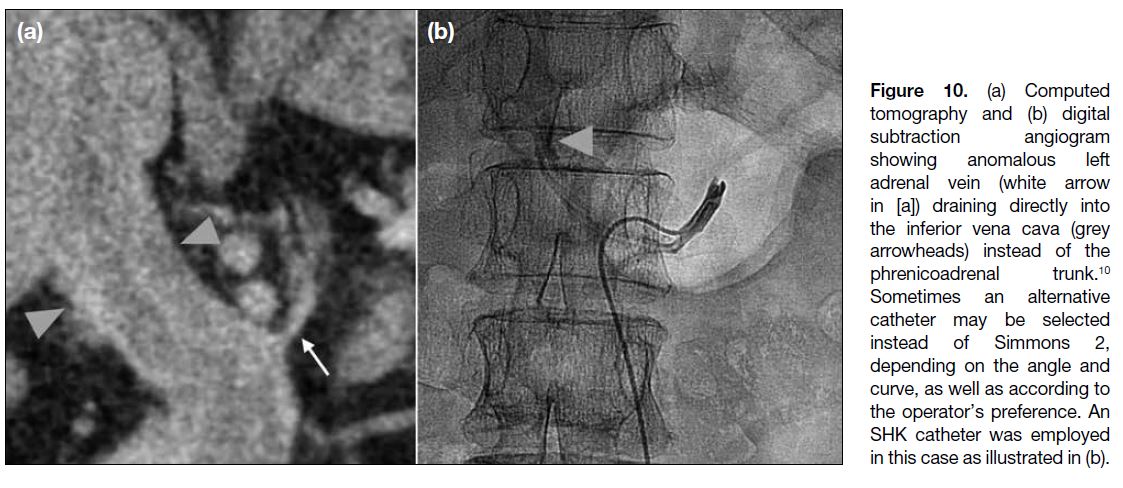

There are anatomical variations of the left adrenal vein

that operators should be aware of. Examples include direct drainage of the left adrenal vein into the left renal

vein without forming a common phrenicoadrenal trunk

with left inferior phrenic vein, or direct drainage into the

IVC[8] [10] (Figure 10). There are also reported cases where

the central vein may be absent or very short, with multiple

adrenal tributaries draining into the phrenicoadrenal

trunk directly or into the inferior phrenic vein without a

central vein.[8]

Figure 10. (a) Computed

tomography and (b) digital

subtraction angiogram

showing anomalous left

adrenal vein (white arrow

in [a]) draining directly into

the inferior vena cava (grey

arrowheads) instead of the

phrenicoadrenal trunk.[10]

Sometimes an alternative

catheter may be selected

instead of Simmons 2,

depending on the angle and

curve, as well as according to

the operator’s preference. An

SHK catheter was employed

in this case as illustrated in (b).